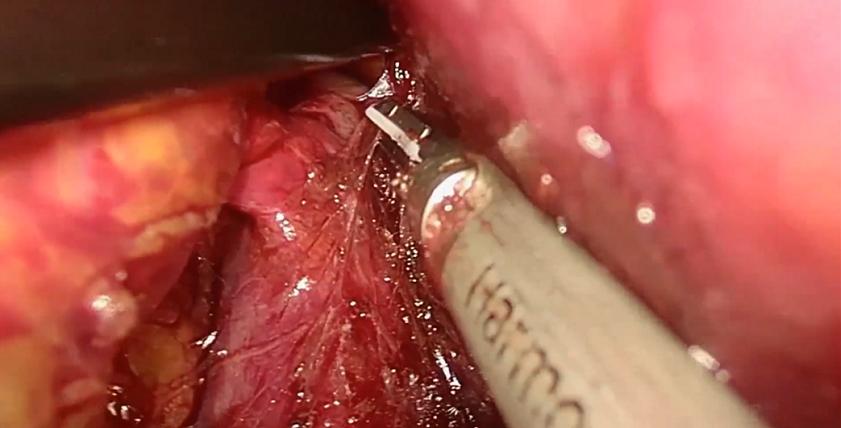

肾上腺肿瘤的下腔静脉瘤栓较为少见,本手术过程中意外发现中央静脉及下腔静脉瘤栓,术中隐约可见瘤栓在下腔静脉里漂荡,可能因瘤栓较细,术前CT难以发现。 由于右侧中央静脉太短,经反复尝试无法通过直接钳夹完整取栓后,术者最终选择切开血管取栓。后腹腔空间小且手术部位位置深,下腔静脉取栓手术难度较高。原则上应阻断瘤栓的近端及远端,但考虑到经后腹腔阻断瘤栓近心端下腔静脉操作困难,难以进行,故选择结扎切断两根肝短静脉、阻断瘤栓远端下腔静脉,然后调高气腹压以对抗减低了的腔静脉压,以达到少出血甚至不出血的目的。 手术演示